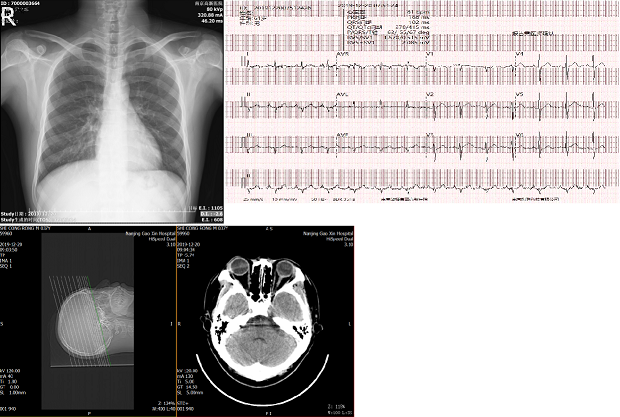

【設備】

B超、胃鏡、腸鏡、

DR、CT、心電(diàn)圖、

肺功能(néng)、骨密度